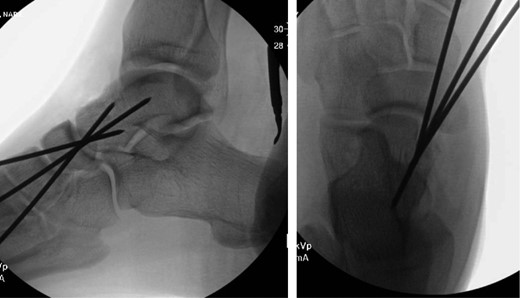

Once general anesthesia was induced, closed reduction was attempted using axial traction with the knee in flexion. Closed reduction was unsuccessful once again (Fig. 3) so the decision was made to attempt open reduction. An anteromedial approach was used dissect down to the talonavicular joint. Retractors were placed with care to avoid injury to tibialis anterior tendon or superficial peroneal nerve. The joint capsule was seen to be disrupted and further exposure revealed a thin, coronal fracture of the anteromedial aspect of the talar head measuring roughly 2 cm in length and 6 mm in thickness (Fig. 4). Once this fragment was removed, the subtalar and talonavicular joints were easily reduced. It was thought that this incarcerated fragment was the likely cause for the unsuccessful closed reduction. The talar head fragment was unamendable for stabilization due to its small size with poor healing potential, thus it was removed. The talonavicular joint was then percutaneously pinned in retrograde fashion with three K-wires (Fig. 5) to maintain anatomic reduction of the subtalar and talonavicular joints and the foot was splinted. At 2 weeks follow-up the patient was doing well and radiographs revealed no interval loss of reduction (Fig. 6).

Intraoperative AP view localizing the medial subtalar dislocation.